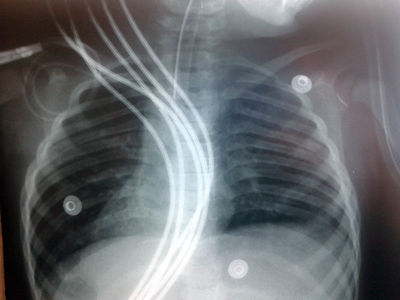

¿Que error "técnico" reconoce en esta radiografía de tórax?

Image:

01f832b8-f66c-4c89-b0a4-ae614d119ce2 (image/jpg)

Answer

Tiene los cables del monitor que obstaculizan la visión correcta del tórax

Está muy penetrada y no se logra ver bien

La radiografía no presenta ningún error técnico, es correcta